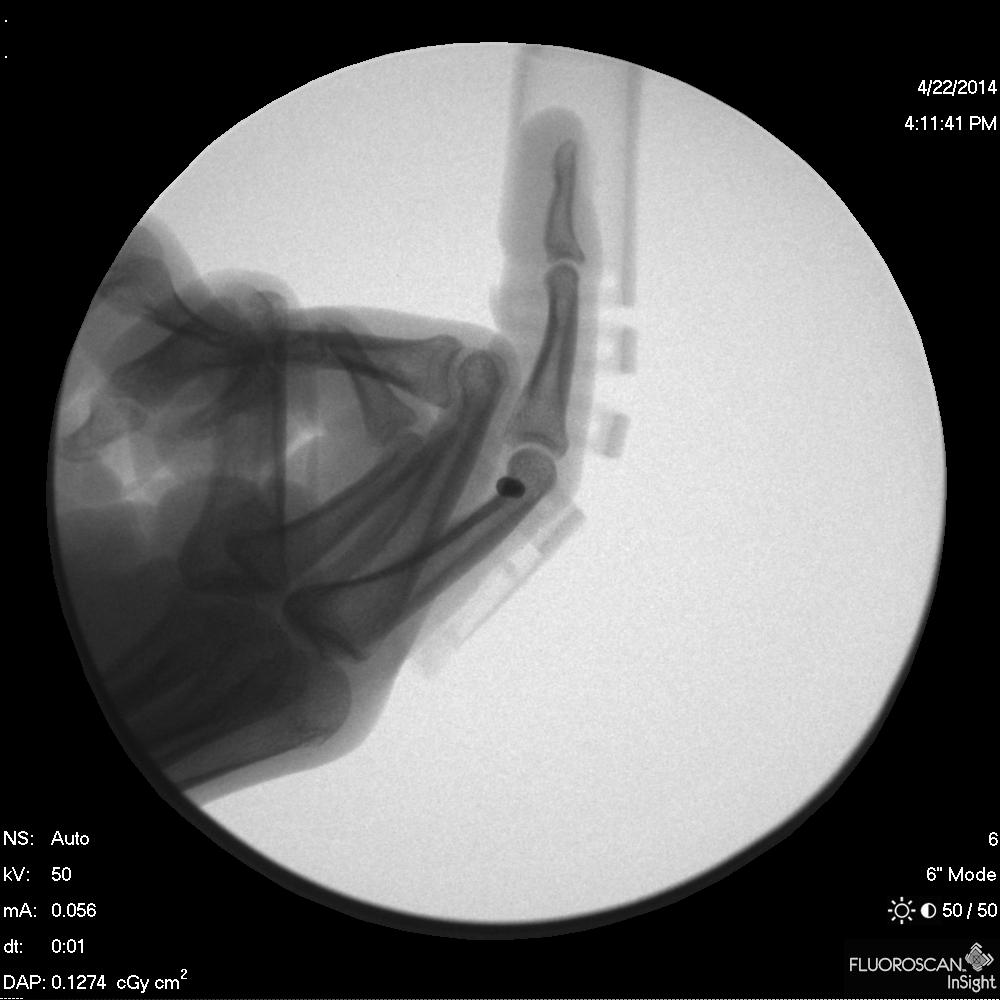

bend, a revolutionary medical finger split